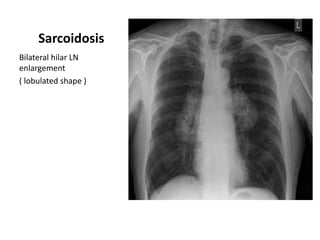

Sarcoidosis

Bilateral hilar LN

enlargement

( lobulated shape )